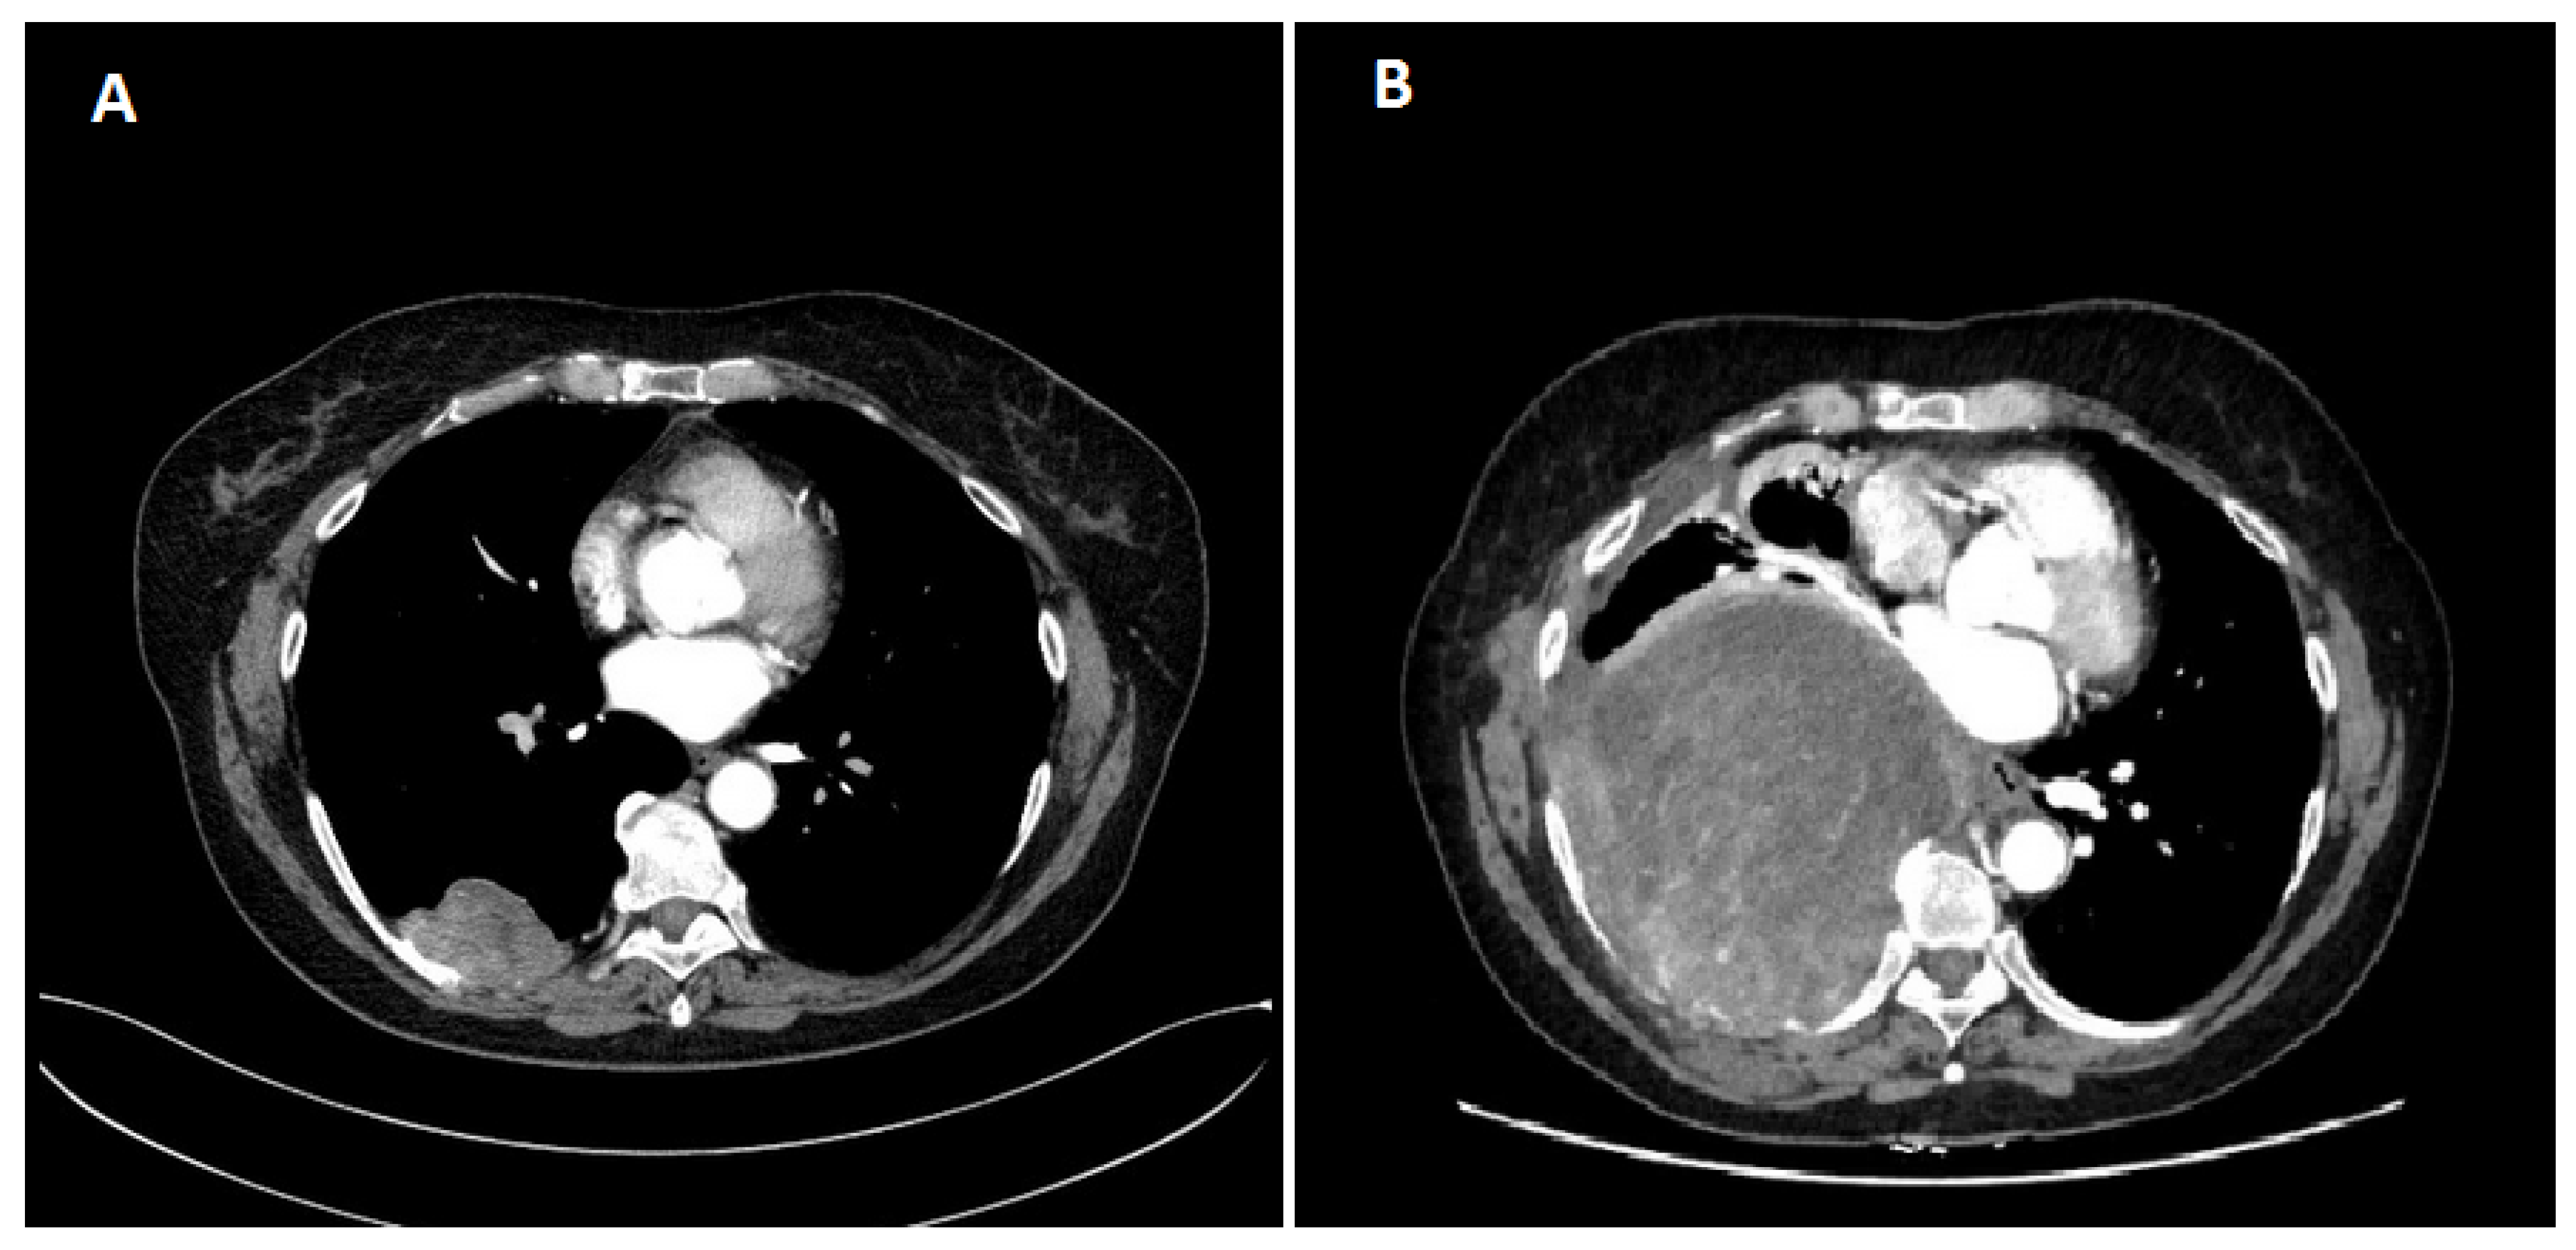

2. Case Report